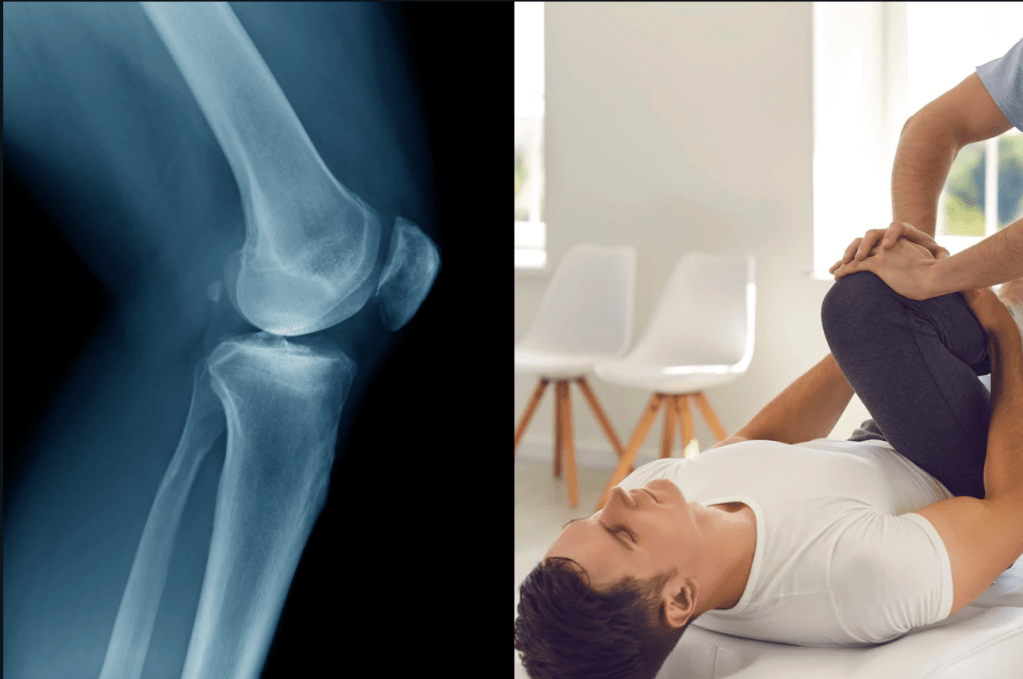

Arthritis is an ever-growing and painful problem. According to a 2022 study by the Center for Disease Control, 18.9% of adults aged 18 to 65 suffer from some form of arthritis (and even that number might be too low). However, scientists from the University of Utah, New York University, and Stanford University have found an old school way to help those with knee osteoarthritis relieve pain without medication or surgery. Their answer? Walk it off.

Their study found that adjusting the angle of a person’s foot when they’re walking and retraining the gait of a person with osteoarthritic knees provided comparable pain relief to medication. On top of that, the participants who adjusted and retrained the gait show less cartilage deterioration over time compared to other participants given placebo treatments.

In the study, 68 participants with osteoarthritic knee pain had MRIs taken, and were split into two groups—one was given a placebo treatment and the other group was trained to walk differently. Both groups then took part in six weekly lab-based training sessions in which participants in the gait training group had a device attached to their shins that guided them to keep their feet at the desired angle while walking on a treadmill. Following the training, the participants practiced their “prescribed gait” for 20 minutes each day until it turned into a natural habit and did follow-up visits to ensure that they stuck to their new gait. After a year, the participants self-reported their experience of knee pain and had a second MRI to assess their knee cartilage after the study, with both showing promising results.

As Ulhrich said, adjusting how you walk to reduce the weight and stress on the knees isn’t a new recommendation from doctors. In fact, it has mostly been recommended to older people experiencing stiffness and pain so severe that it’s hard to move. And while gait retraining is mostly recommended by the Arthritis Foundation, one main issue is that it takes concerted effort and time from both patients and the doctors to ensure that the retrained gait becomes a permanent habit.

That said, this effort is necessary compared to other current pain management options. There is a global concern about osteoarthritic patients becoming addicted to the pain medication they’re prescribed for their ailment, creating a great need for alternative techniques and treatments to reduce pain. However, according to doctors like Ulhrich, this study reveals that this can be a way for younger people to manage their pain and develop a permanent habit that can improve and extend their quality of life until more drastic treatment measures need to be taken.

“Especially for people in their 30s, 40s, or 50s, osteoarthritis could mean decades of pain management before they’re recommended for a joint replacement,” Ulhrich said. “This intervention could help fill that large treatment gap.”